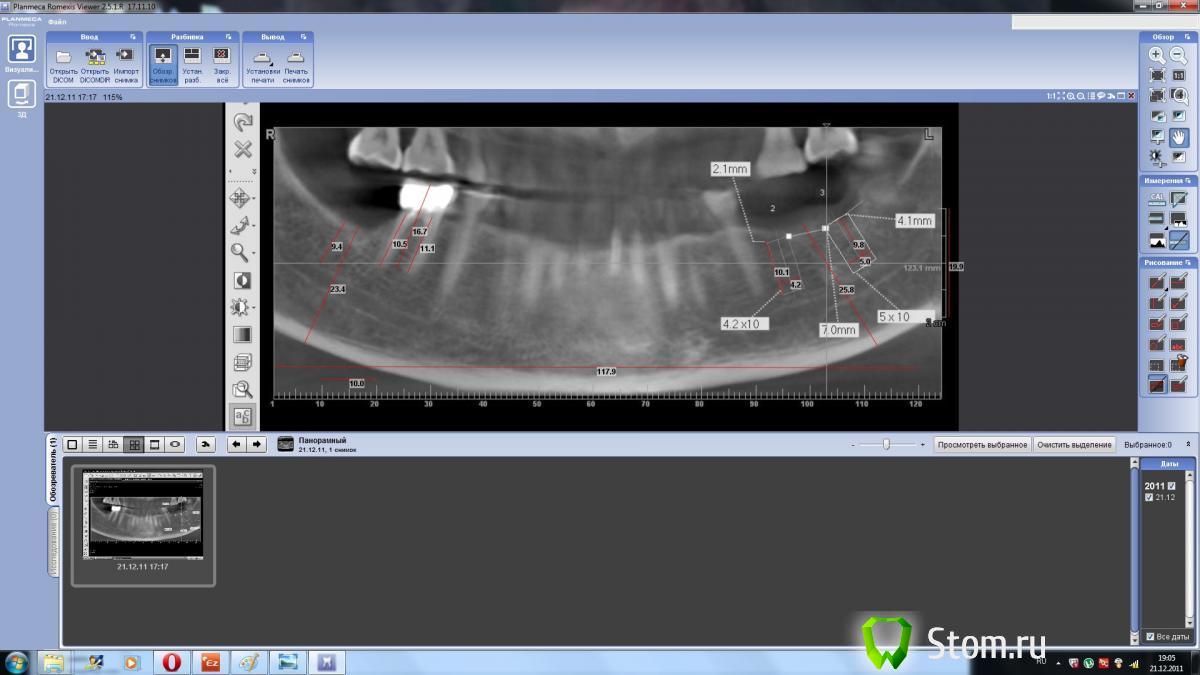

dent-a Опубликовано 21 декабря, 2011 Поделиться Опубликовано 21 декабря, 2011 Предыстория. КЛКТ на ватэке сделано в уважаемой фирме. Открыл, просчитал, получилось всё хорошо, сделал пару снэпов (фоток) рис 1. Дело было на работе вечером (windows xp). На следующий день то же самое (перепроверка) - но на домашнем компе (win 7) - открываю и результаты совсем иные рис 2 .... Сделал опять снэпшоты. Потом взял то - что просчитал днём ранее и экспортировал в планмековский считовод. Откалибровал в нём всё и .... всё оказалось верно рис 3. Где правда - то ?)) Позвонил в фирму....но там ко мне применили приём, как говорит один знакомый доцент, "мягкий посыл"... ну и на всякий им ещё в почту скинул. Раньше делал кт планмека в более дорогом месте...видимо и дальше буду делать дороже, т.к. таких аномалий не было. Поделитесь цифровым опытом. Может просто горе от ума :? Ссылка на комментарий